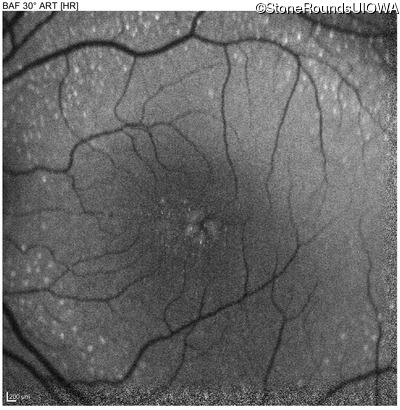

Blue Autofluorescence - Right - 20/32 -1

Exemplar